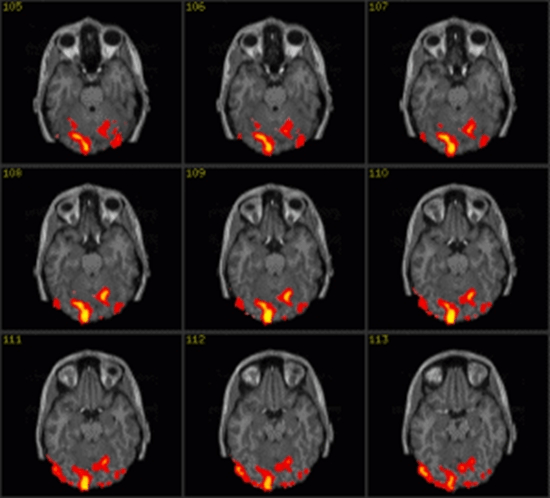

بررسی ارزش تشخیصی تصویربرداری پذیرفتاری مغناطیسی در نمایش ویژگی های تصویری تومورهای مغزی گلیال در مقایسه با سکانس های روتین تصویربرداری MR

تصویربرداری پذیرفتاری مغناطیسی در نمایش ویژگی های تصویری تومورهای مغزی گلیال